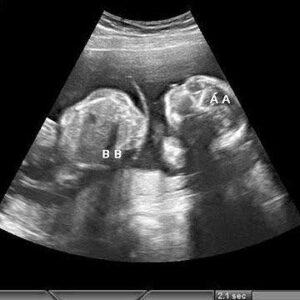

Perheen lähipiirilähteet kertovat, että pari jakoi yksityisesti ultraäänikuvia läheisen piirin kanssa ennen kuin uutinen alkoi levitä, mikä herätti nopeasti spekulaatioita fanien keskuudessa ympäri maailmaa. Vaikka tunnetusti yksityisyyttään kunnioittava pari ei ole antanut täysin yksityiskohtaista julkista lausuntoa, sisäpiiriläiset ovat jo kutsuneet uutisoitua paljastusta “kaksospommiksi”, mikä heijastaa sekä yllätystä että iloa, joka liittyy kehitykseen.

Tilanteeseen perehtyneiden mukaan ultraäänikuvat vahvistivat terveen kaksosraskauden, mikä herätti iloa perheenjäsenten ja läheisten ystävien keskuudessa. Vaikka tärkeitä yksityiskohtia, kuten laskettu aika, sukupuoli ja nimet, ei ole julkistettu, sisäpiirilähteet viittaavat siihen, että valmistelut ovat jo käynnissä, kun perhe valmistautuu toivottamaan tervetulleeksi kaksi uutta tulokasta.